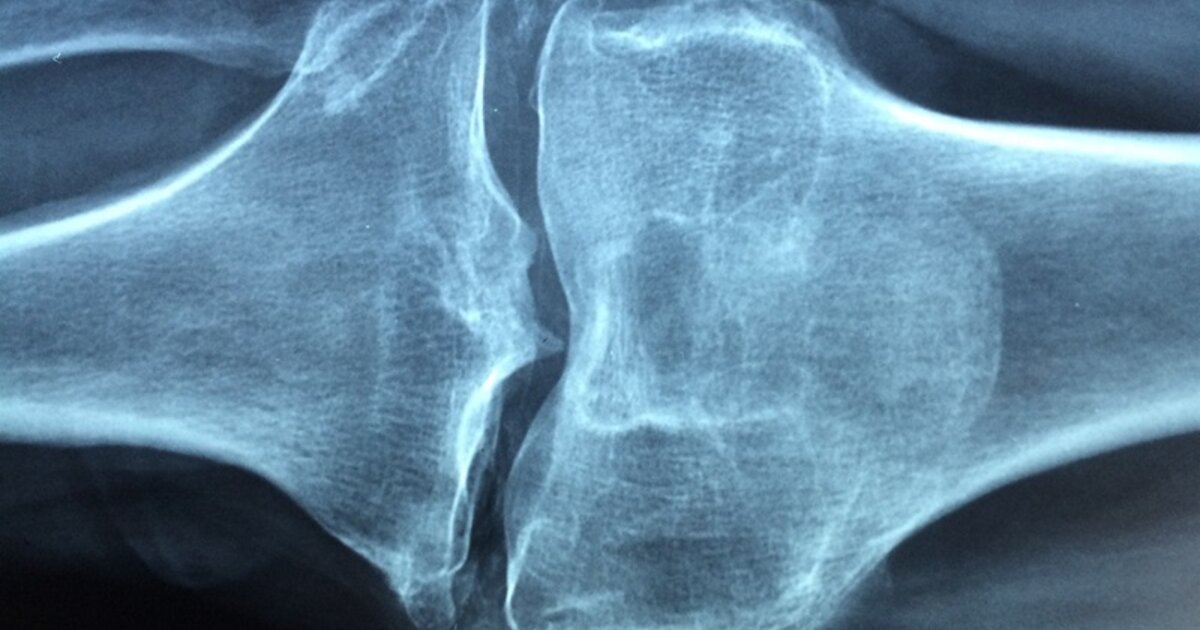

Φωτογραφία από Dr. Manuel González Reyes από το Pixabay